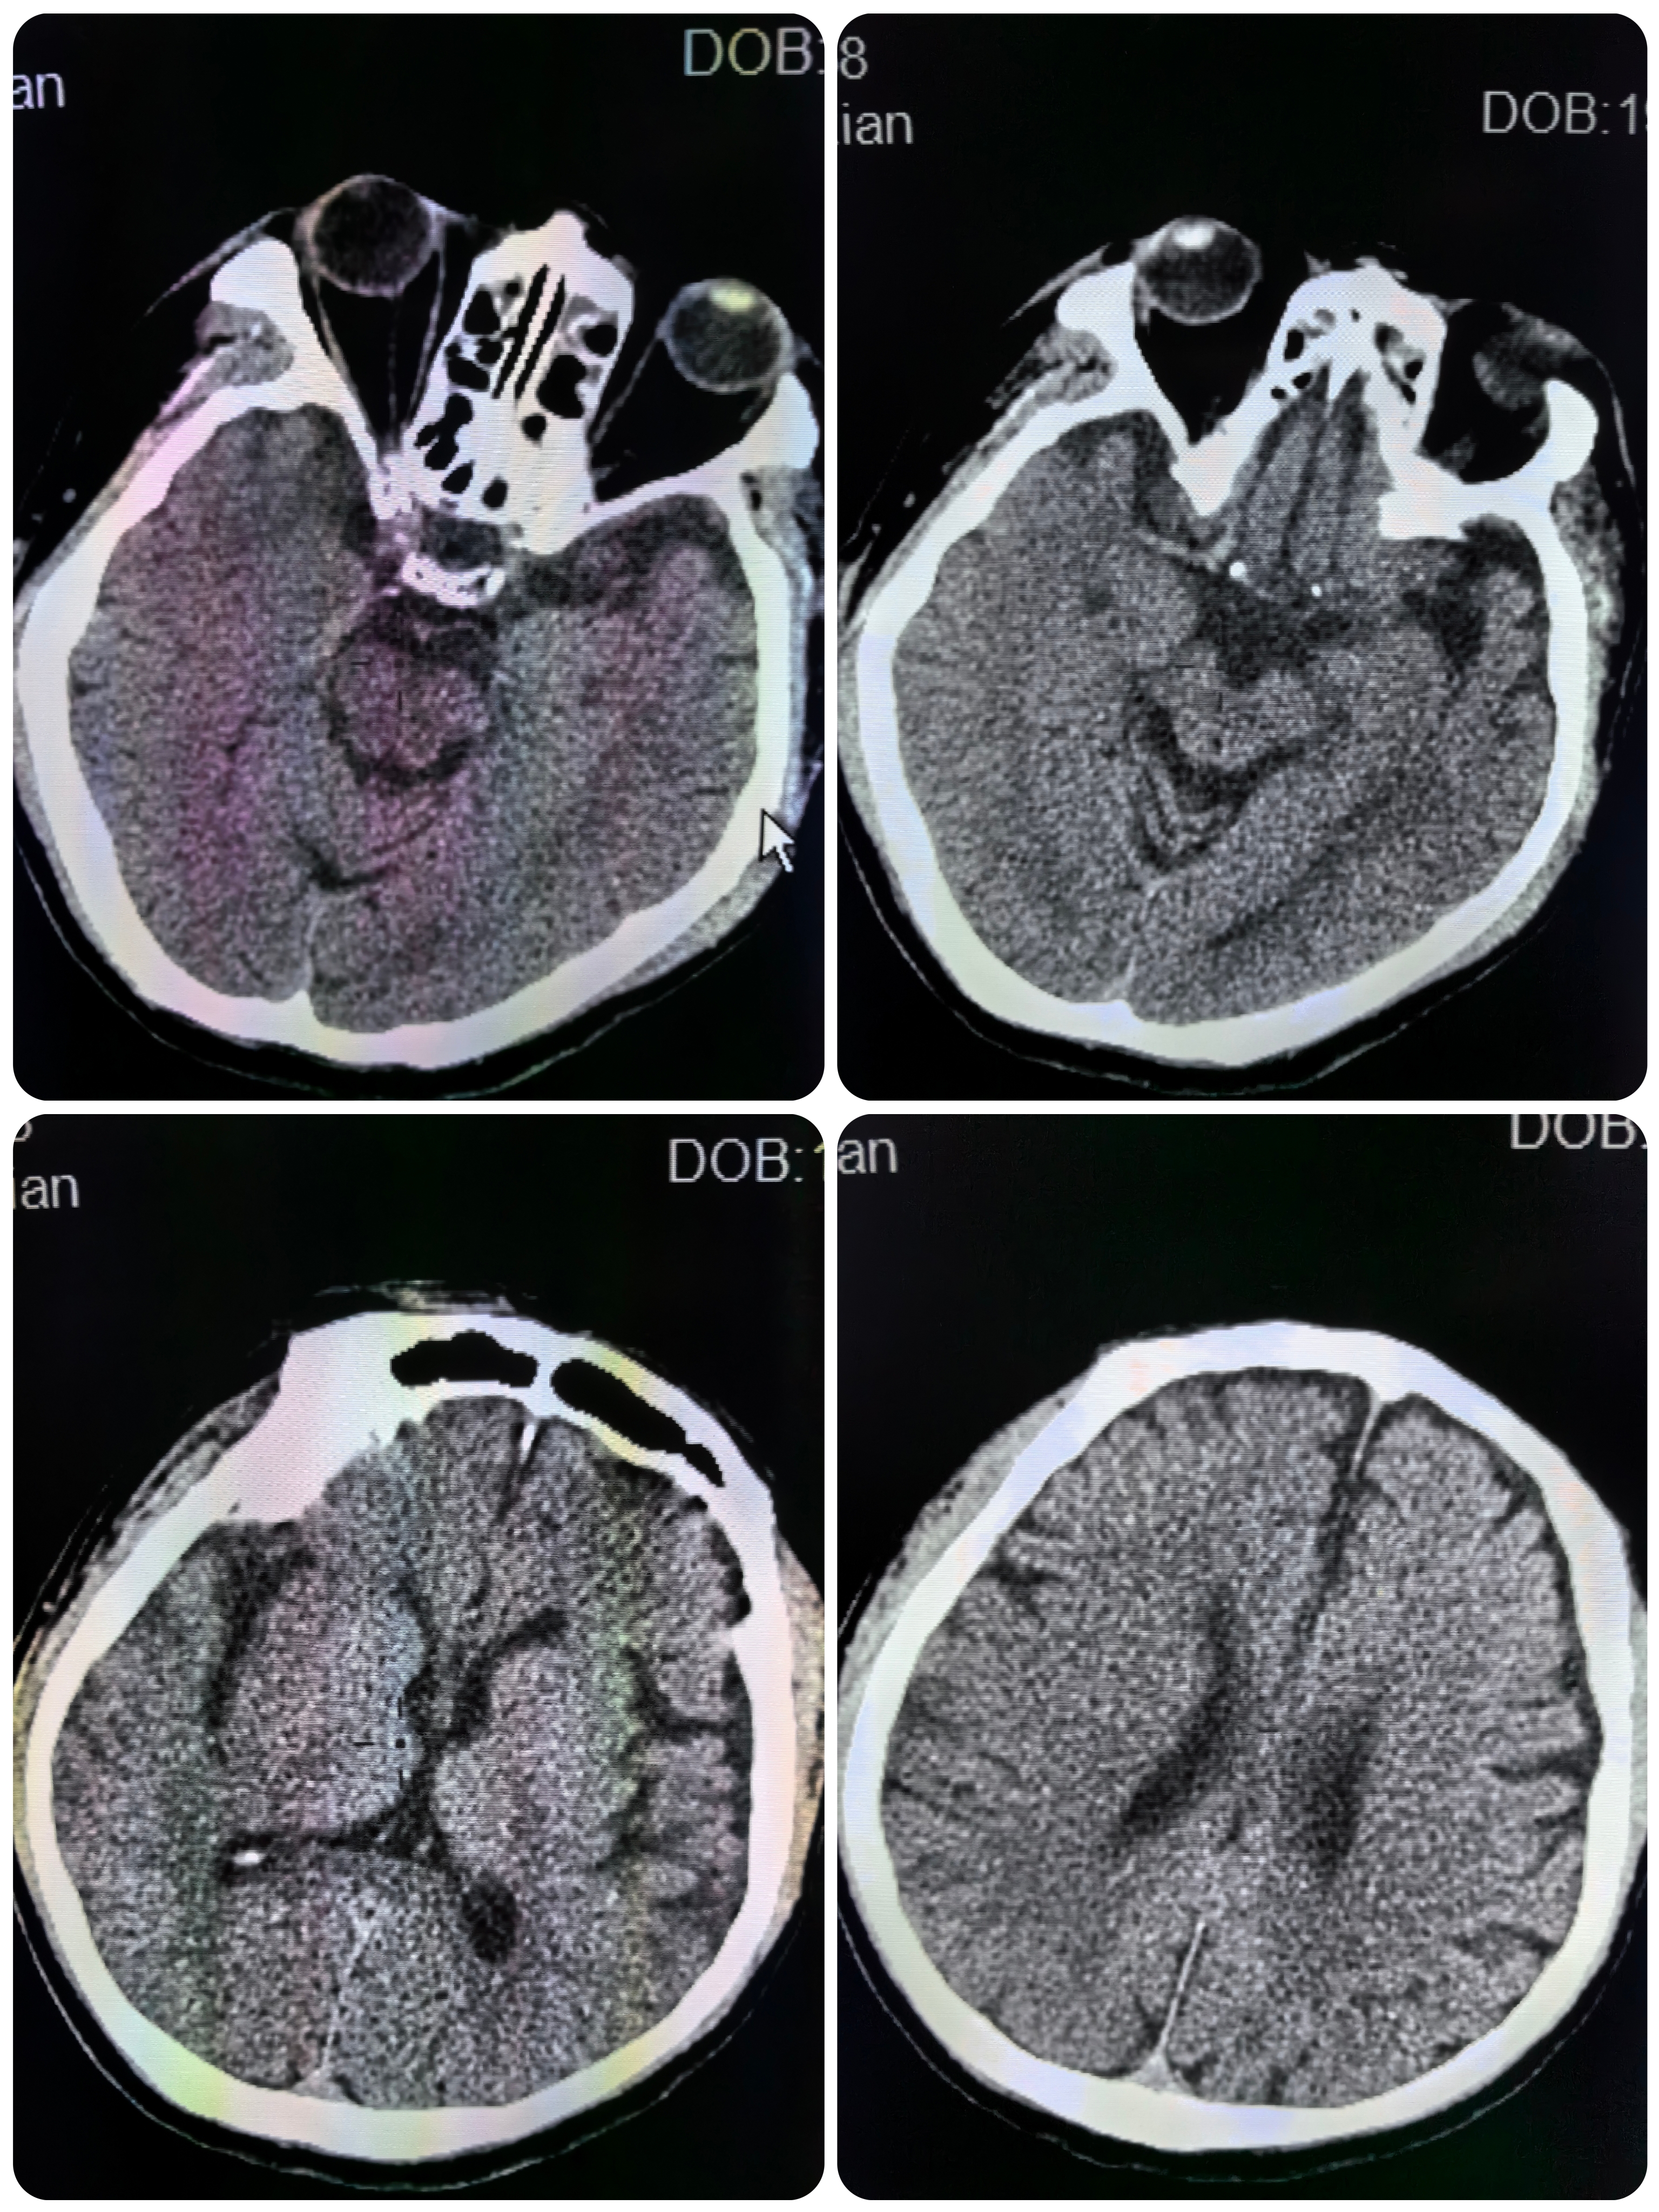

患者男性,59岁,突发左侧肢体活动失灵2小时,既往房颤病史,口服比索洛尔。查体:血压125 /80mmHg,心率80次/分,神清构音障碍,左侧肢体肌力0级,左侧偏身感觉减退,左侧病理征(+)。NIHSS评分12分。

1、本例患者起病急骤,右侧凝视,左侧偏瘫,CT可见右侧大脑中动脉高密度征,发病2小时,给予静脉溶栓后症状未见缓解,遂桥接血管内治疗。